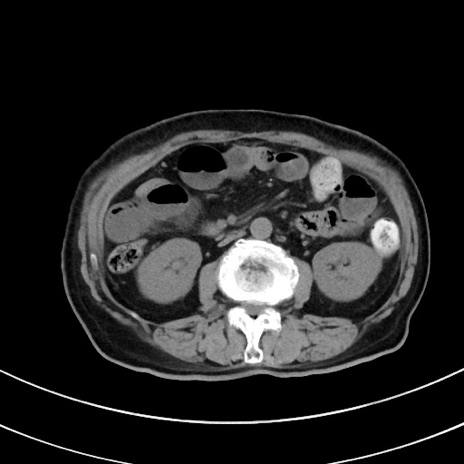

症例33(横断像)

【症例】70歳代 女性

【主訴】心窩部痛

【身体所見】右下腹部を中心に圧痛と反跳痛あり。

【データ】WBC 10900、CRP 0.02